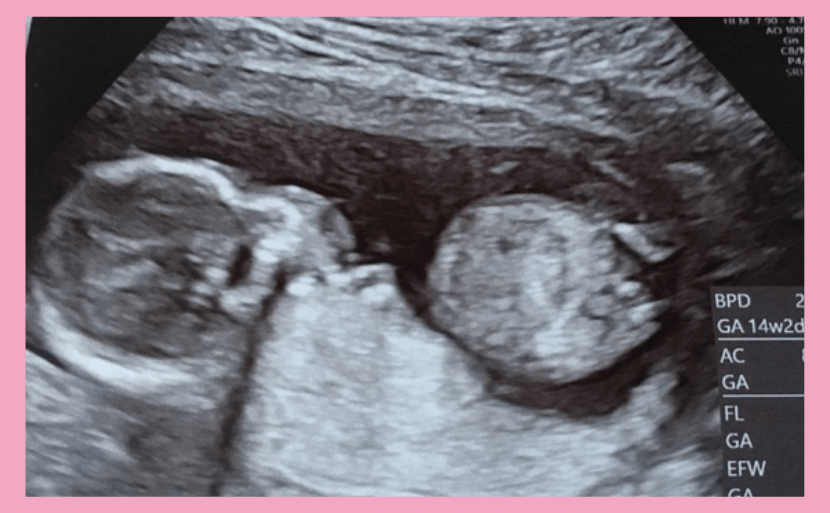

妊娠14週の赤ちゃん

お腹の中の赤ちゃんの状態

妊娠14週を迎えると胎盤が完成に近づき、へその緒から栄養を摂取する準備が始まります。それにともない胎児の各器官や筋肉、また首や手足が発達する時期です。皮下組織(脂肪)は形成されていませんが、少しずつ皮膚が厚みを増し、産毛が生え始めます。心臓もしっかり拍動し、赤ちゃんの心拍数は1分間に約150回となります。お母さんの心拍数(1分間に約60〜70回)と比べ、倍以上の心拍数といえるでしょう。

妊娠14週の赤ちゃんの大きさはCRL(頭殿長)約90mm、体重は20〜25gほどとされています。腹部エコー検査では赤ちゃんの胃泡が見えたり、膀胱におしっこが溜まる様子が映されることも。妊娠14週は羊水内で赤ちゃんが身体の向きを変え、活発に手足を動かし運動を始める頃です。しかし胎動を感じるのは、もう少し先の妊娠18週以降となります。

妊娠14週目のエコー写真です。